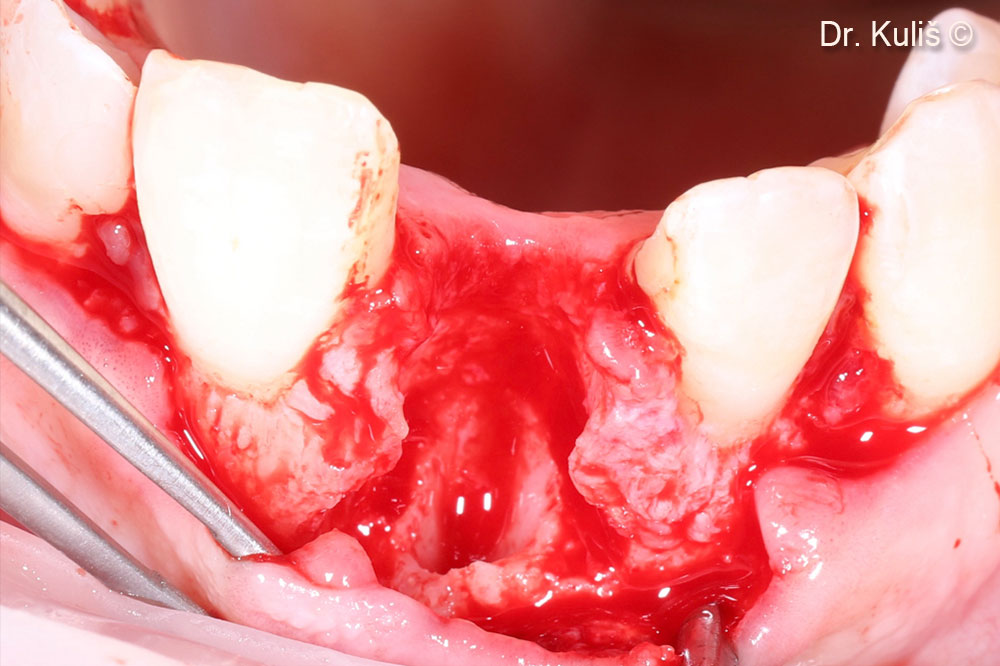

Khuyết tật xương má sau khi nhổ răng và loại bỏ mô hạt